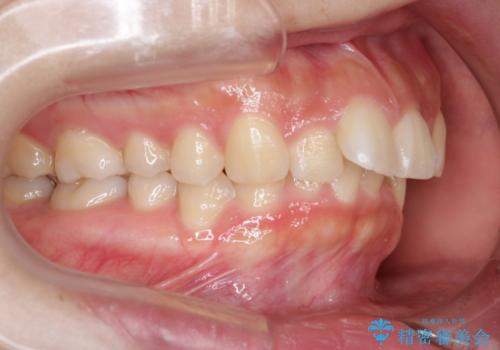

- 治療計画

- 前歯のがたつきが気になるとご相談にいらした方です。当初は前歯の部分矯正をご希望されていましたが、全体的に整えることで審美的、機能的な歯並びとなりました。

当初は上顎前歯のみの部分矯正をご希望されていましたが、部分的に前歯のみを並べると出っ歯感がつよくなり、食事もしづらくなる可能性をお伝えしました。全顎的な矯正治療により、審美的、機能的な歯並びとなりました。